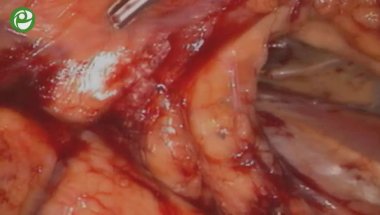

Лапароскопическая роботизированная нервосберегающая радикальная простатэктомия

24 дек 2015

Лапароскопическая роботизированная радикальная простатэктомия, расширенная тазовая лимфаденэктомия

29 дек 2015